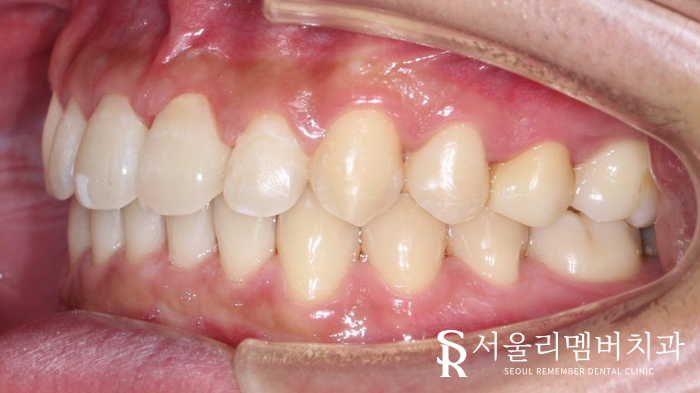

약 11개월이 지나고

사당 치과 의 모든 과정이 마무리되었는데요.

전 모습은 기억이 나지 않을 정도로

긴밀하게 배열된 치아를 볼 수 있었습니다.

훨씬 심미적으로 바뀐 것은 물론이며

음식이 잘 끼는 불편감도 사라졌다는데요.